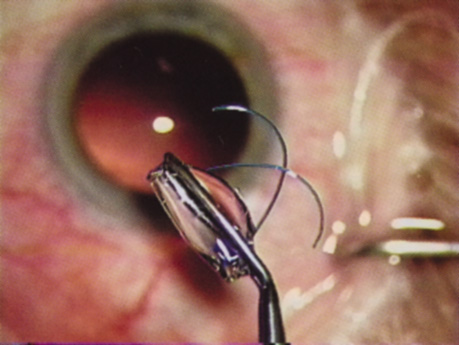

Many patients are most bothered by cataract-induced glare. For these patients, acuity testing under glare situations is indicated. There are several methods to assess visual acuity reduction by glare. The choice of method is often best dictated by the patient's history. If a patient complains of glare problems in the supermarket, or other uniformly illuminated environment, the brightness acuity test can be performed (Mentor Ophthalmics). For this test, the specially illuminated handpiece is held in front of the tested eye using best spectacle correction (Fig. 1). The Snellen acuity is rechecked and can be recorded on each of three light settings.